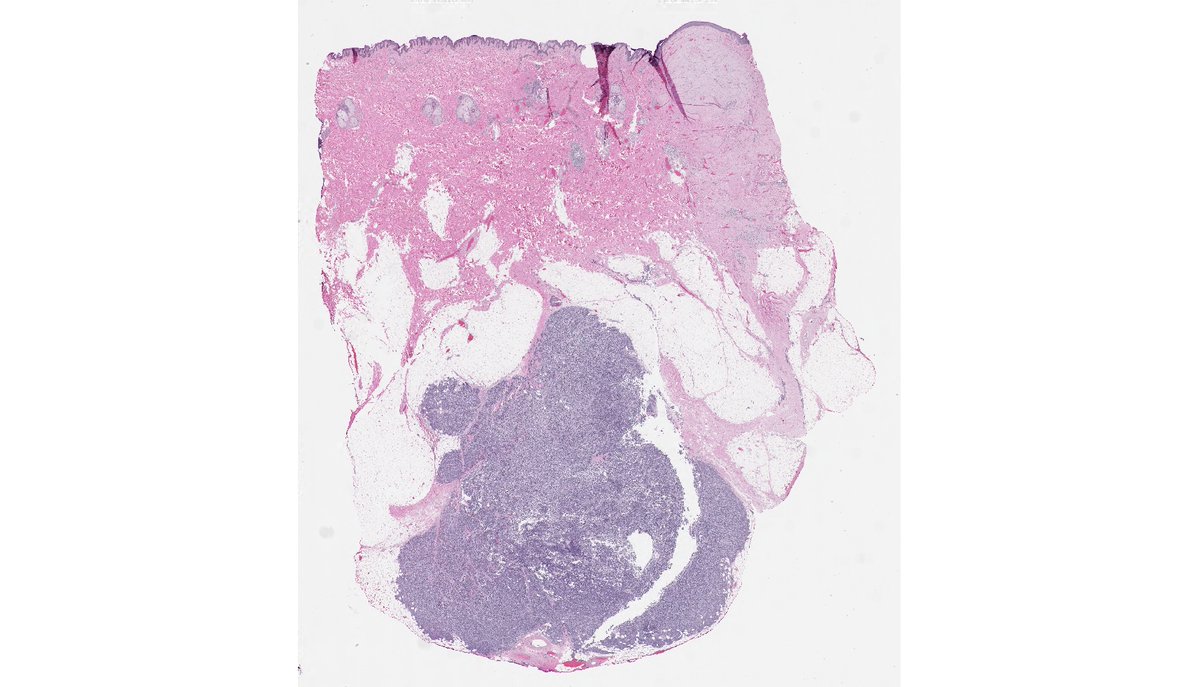

65 yo F 1.5 cm L elbow st mass “r/o gout” CALCIFIED EPITHELIOMA OF MALHERBE WITH OSSIFICATION - firm nodule/mass - keratinized “ghost cells” + bone - focal marrow elements - aka OSSIFIED PILOMATRIXOMA! - aka OSSIFIED PILOMATRICOMA!

#bstpath#dermpath#pathology#nyupathologypic.twitter.com/f3rq7SJIwk